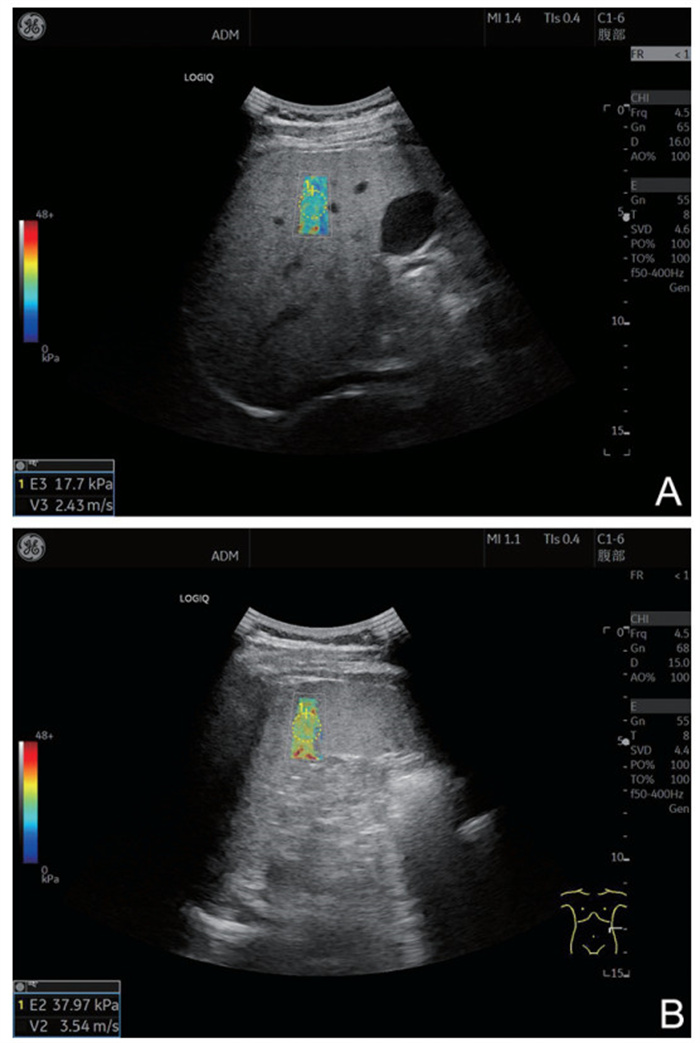

•   Objective  The pathophysiological mechanism of esophageal and gastric varices (EGV) rebleeding in liver cirrhosis is complex, and the mortality rate is high. Identifying the literature factors of EGV rebleeding is important to reduce the mortality rate. Two-dimensional shear wave elastography (2D-SWE) can evaluate the degree of liver hardness and pathological changes in a non-invasive and quantitative manner. This study discusses the construction of the EGV rebleeding risk model based on 2D-SWE to provide a reference for clinical prevention and treatment.  Methods  A total of 162 patients with EGV with cirrhosis admitted to Zhengzhou Central Hospital Affiliated to Zhengzhou University from January 2020 to December 2022 were selected. According to whether rebleeding occurred, the patients were divided into the no rebleeding group (127 cases) and the rebleeding group (35 cases). The risk factors of EGV rebleeding in patients with cirrhosis were analyzed by Logistic regression. To construct a nomogram prediction model for the EGV rebleeding in cirrhotic patients, and evaluate the prediction efficiency of the nomogram model.  Results  The proportion of Child-pugh grade A liver function, the proportion of mild esophageal and gastric varices and the level of ALB in the group without rebleeding were higher than those in the group with rebleeding (P < 0.05), and the proportion of first ligation, liver hardness and spleen hardness in the group with no rebleeding were lower than those in the group with rebleeding (P < 0.05). Logistic multivariate results showed that Child-Pugh grade of liver function, liver hardness, spleen hardness, and ALB were independent influencing factors for EGV rebleeding in cirrhosis (P < 0.05). A nomogram model for predicting EGV rebleeding in cirrhosis was established according to the logistic multi-factor results, and the model was verified. ROC curve analysis results showed that the C-index of the nomogram model was 0.903 (95% CI: 0.846-0.975), and the measured value of the nomogram model was basically consistent with the predicted value, with high predictive value and good clinical effectiveness.  Conclusion  2D-SWE detection of liver and spleen hardness is a risk factor for EGV rebleeding, and the prediction model based on this nomogram has a good predictive effect on EGV rebleeding.